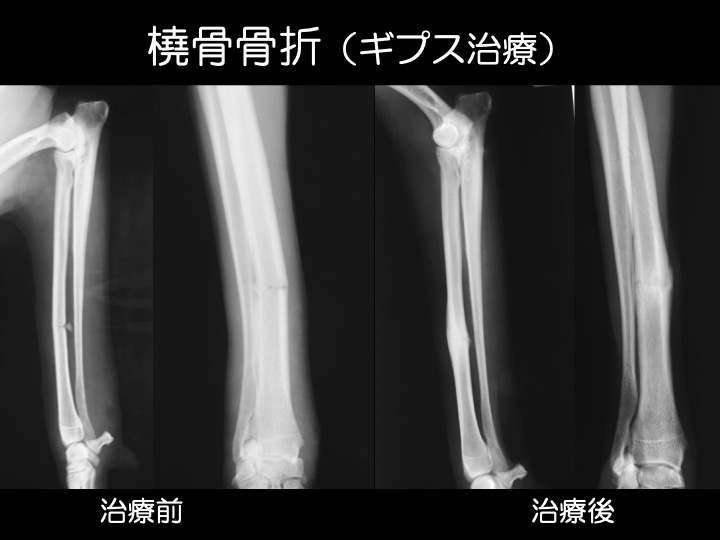

ギプス治療例

・骨折による“骨のズレ”が小さい場合、ギプスによる治療が可能です。多くの場合、全身麻酔を必要としないため、動物の負担も少なく済みます。

【ギプス(外固定)】

・骨折による骨のズレが小さい場合などが適応となります。

・手術前後の一時的な固定として使用されることもあります。

・多くの場合、全身麻酔を必要としません。